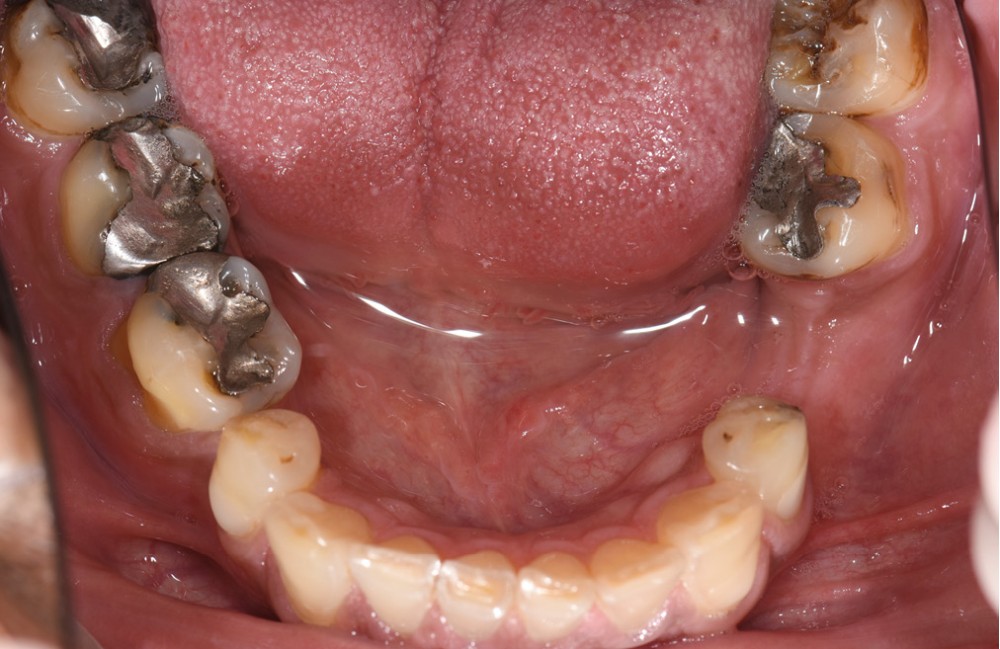

L’usure dentaire est de plus en plus fréquente au sein de nos cabinets. Nos patients y sont sujets de par leur alimentation parfois plus acide, leur mode de vie souvent plus stressant, et également une hygiène qui s’améliore et des dents qui vieillissent davantage.

L’étiologie de cette usure est multifactorielle, revêtant une composante de type attrition (usure par contact dento-

dentaire), une composante abrasive avec un brossage traumatique et, en dernier lieu, une légère composante tribo-érosive de par une pratique importante de sport avec gel et boisson acide (fig. 1-4) [1].